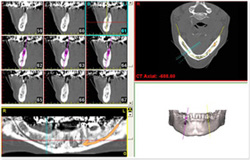

CTを使用した診断を行うことにより、歯根の解剖学的形態の把握が可能になります。

CT診断で分かること

・歯根の湾曲

・根管の数、湾曲

・破折の有無

・根尖病変の広がり程度

・骨の状態

・破折器具の有無

CT画像を見ると根管が2本あることが分かりました。(レントゲンだけでは分かりませんでした。)

| 治療説明 | 右下第2小臼歯、他院で根管治療した後に頬側根尖部から排膿があます。X線CT画像では、根管が2本あり、そのうち舌側が根管充填されていませんでした。顕微鏡下で2根管とも根管充填処置を行い、4ヶ月で、X線透過像は消失しました。 |

Simplant |

CT画像データを用いた、インプラント治療シミュレーション。 |

GC:Planmeca製 CTです。

5年前に導入しましたデジタルパノラマをCTへバージョンUPしました。

上下顎を3ブロックに分けて撮影できるため、必要な部分だけ撮影できます。

今まではCT撮影というと、インプラント治療のための術前診断のためがほとんどでした。

しかしソフト・ハードウエア両面の進歩により画像解析機能が飛躍的に向上し、従来の2次元のX線写真では判らなかった歯周病による骨吸収状態や、歯根の先端に生じた病巣の状態を3次元的に診断することが可能となりました。

被曝線量も胸部X線写真と変わらない程僅かです。